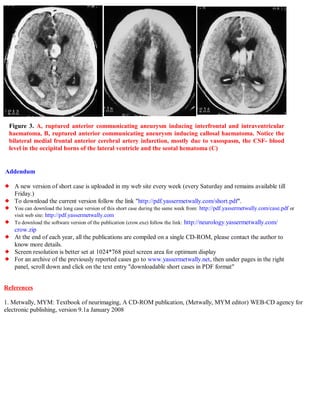

A 40-year-old male patient was found unconscious on a toilet with a ruptured anterior communicating artery aneurysm and subarachnoid hemorrhage. CT scans showed interfrontal subarachnoid hemorrhage breaking into the ventricles with blood in the occipital horns and bilateral anterior cerebral artery infarctions, more severe on the right side. The document describes images of the ruptured anterior communicating artery aneurysm and associated hemorrhaging and edema. It also provides information on accessing updated case publications on the author's website.